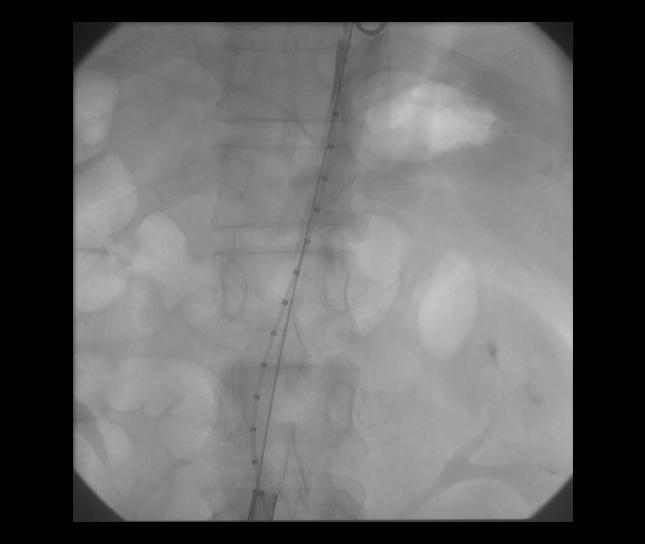

EVAR